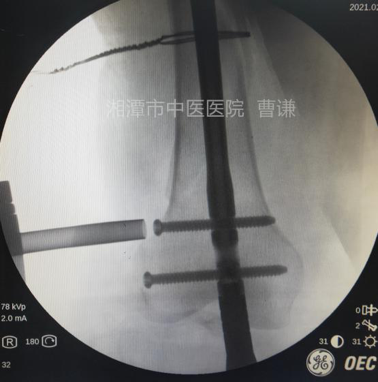

通过正侧位透视进钉点位置,正位位于髁间窝中点稍偏外侧,侧位位于Blumensaat线稍前方。避免损伤后交叉韧带及髓内钉穿出后侧皮质。

扩髓后沿导针置入髓内钉,注意尾端不要突出髁间窝,髓内钉尖端应置于小转子水平。

安装瞄准器后分别置入远端锁钉及近端锁钉,透视锁定良好。